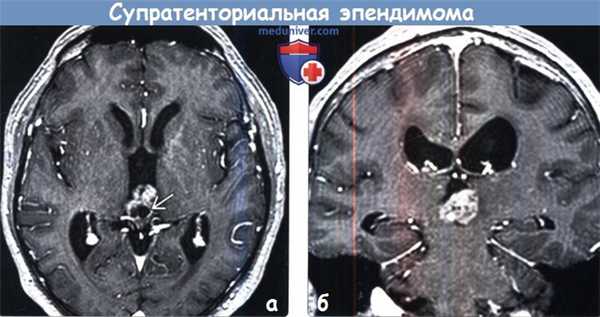

(а) МРТ, Т2-ВИ, аксиальный срез: у пациента с супратенториальной эпендимомой (СТЭ) в III желудочке определяется негомогенное объемное образование. Обратите внимание на относительно низкую интенсивность сигнала, мелкие кистозные компоненты в структуре опухоли.

(б) МРТ, Т2* GRE, аксиальный срез: у того же пациента определяются участки «выцветания» изображения и очаги гипоинтенсивного сигнала, представляющие собой кальцификаты или кровоизлияния.

(а) МРТ, постконтрастное Т1-ВИ, аксиальный срез: у того же пациента определяется выраженное, но негомогенное накопление контраста. В структуре опухоли отмечаются солидные и кистозные компоненты различных размеров и более крупный кистозный компонент с краевым характером контрастирования.

(б) МРТ, постконтрастное Т1-ВИ, корональный срез: у того же пациента определяется негомогенное контрастирование узлового компонента образования внутри III желудочка.